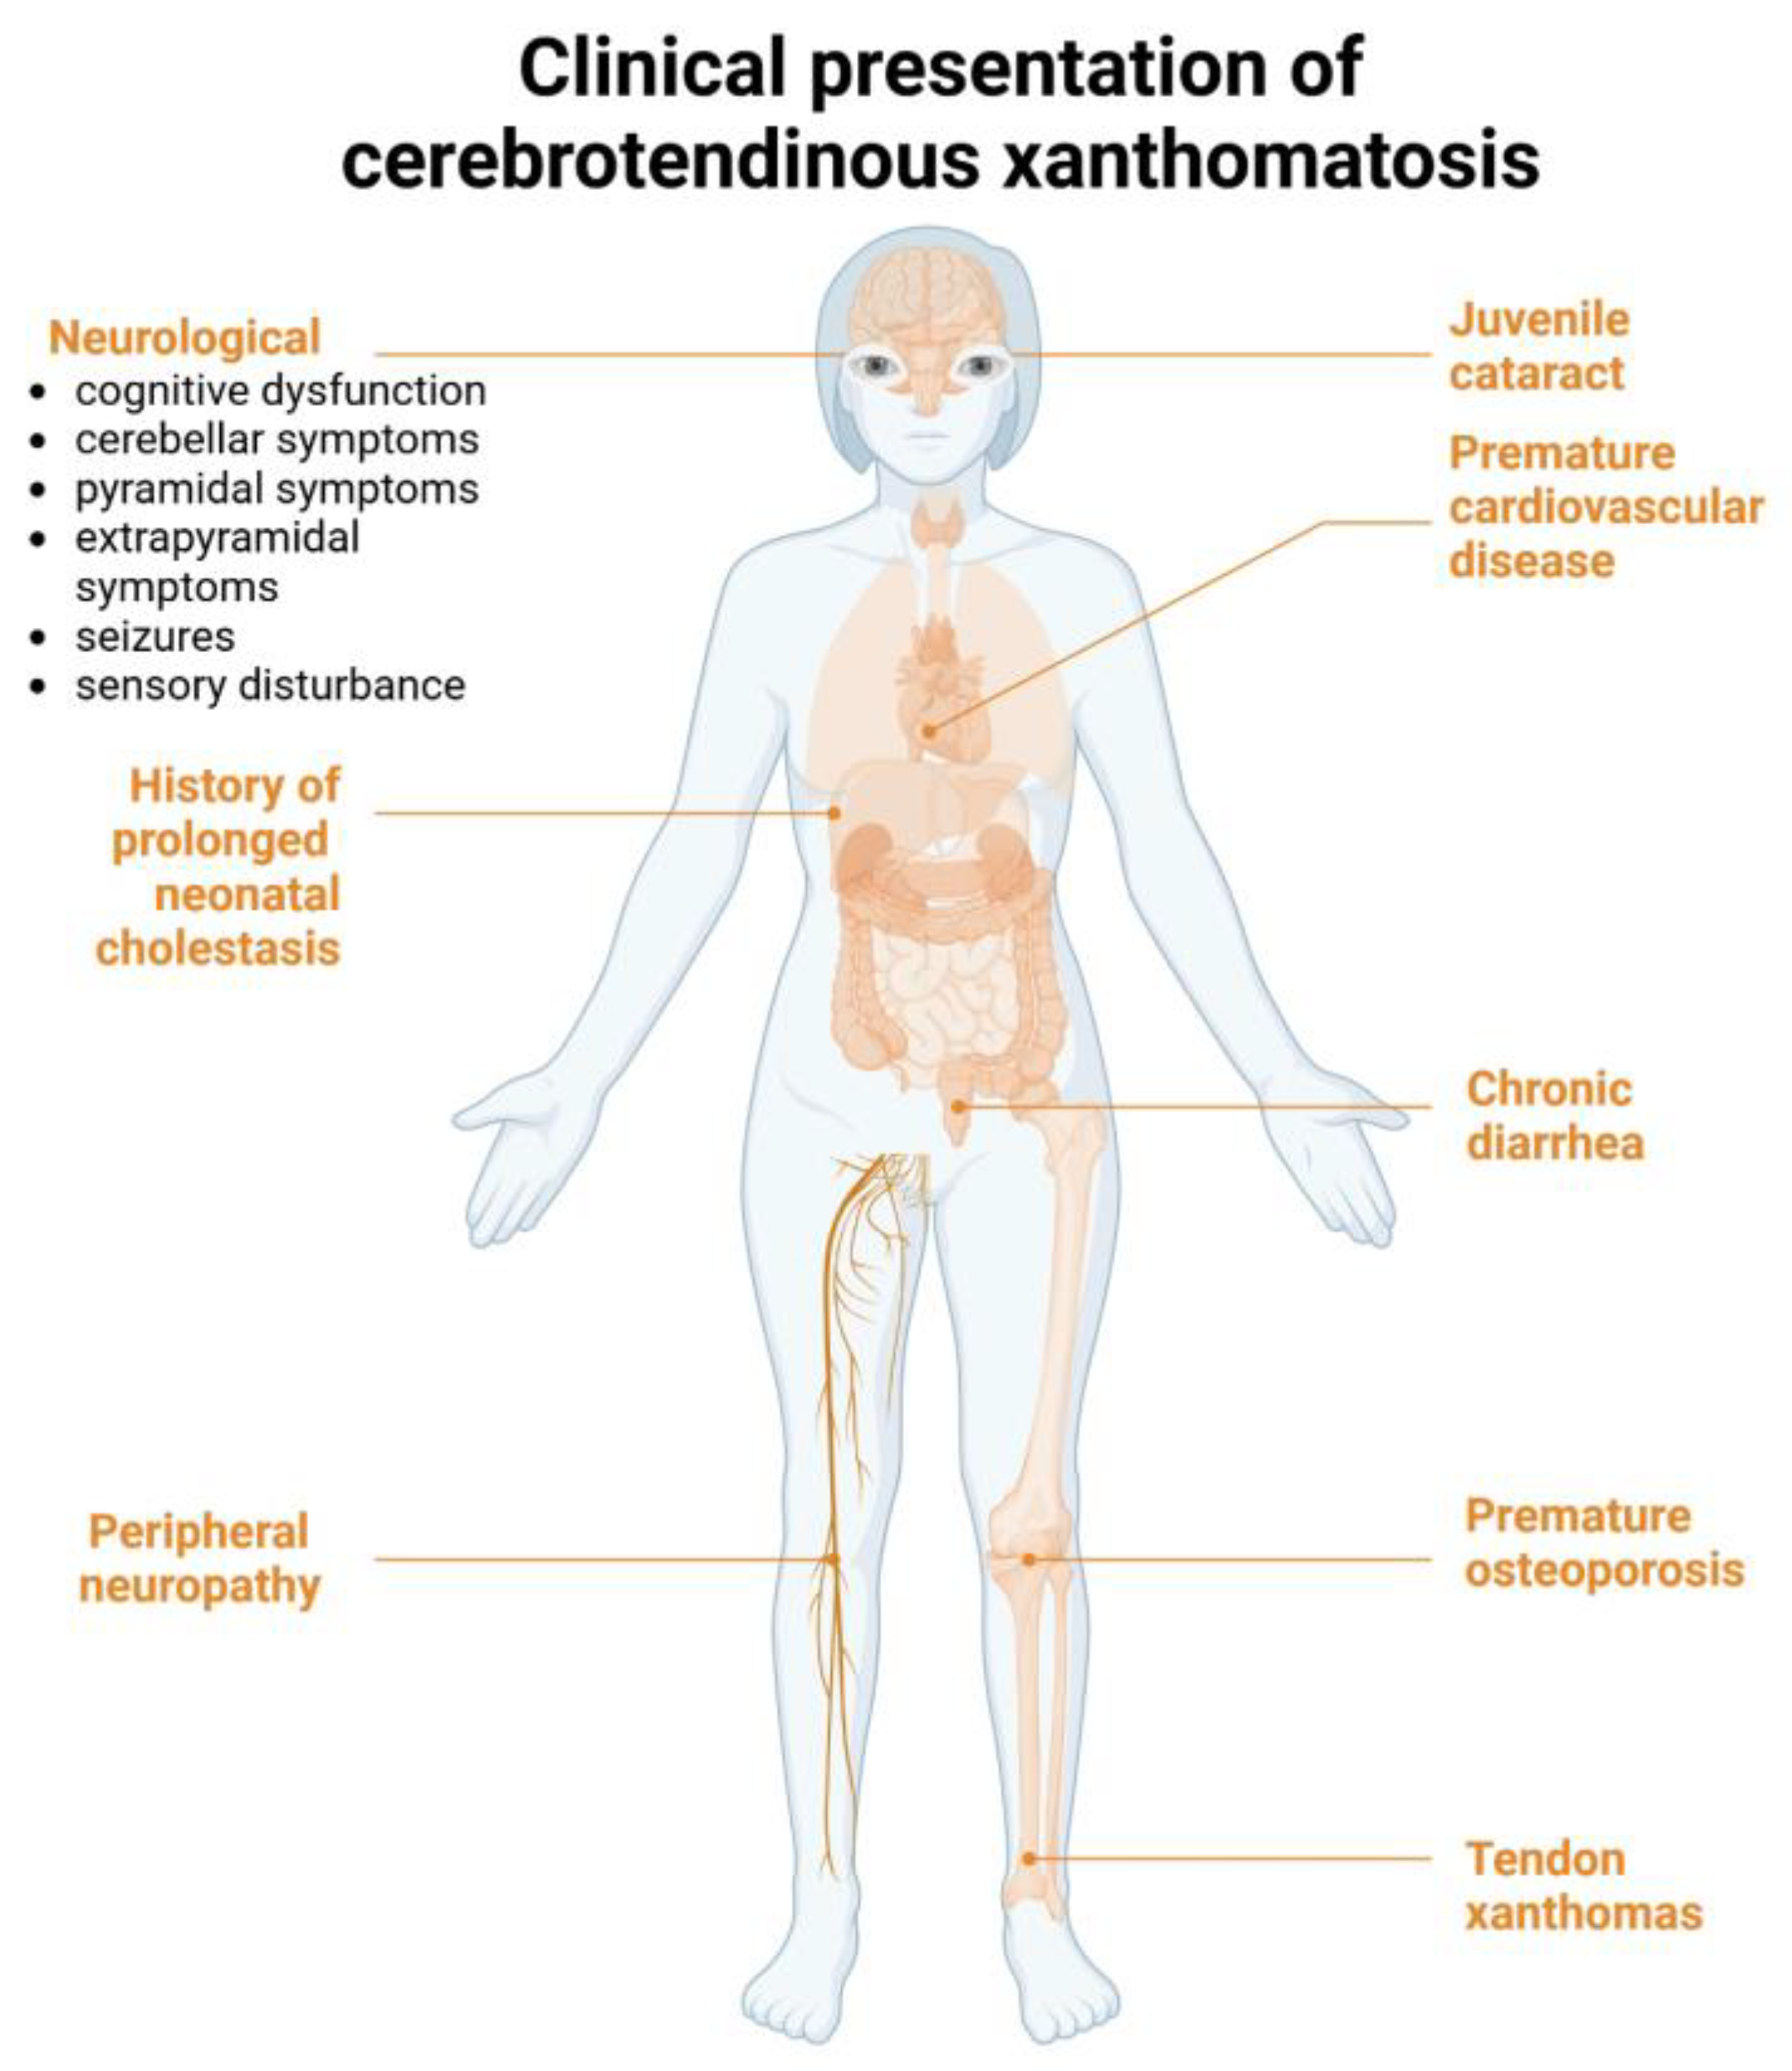

1. Introduction and Clinical Significance

3. Discussion